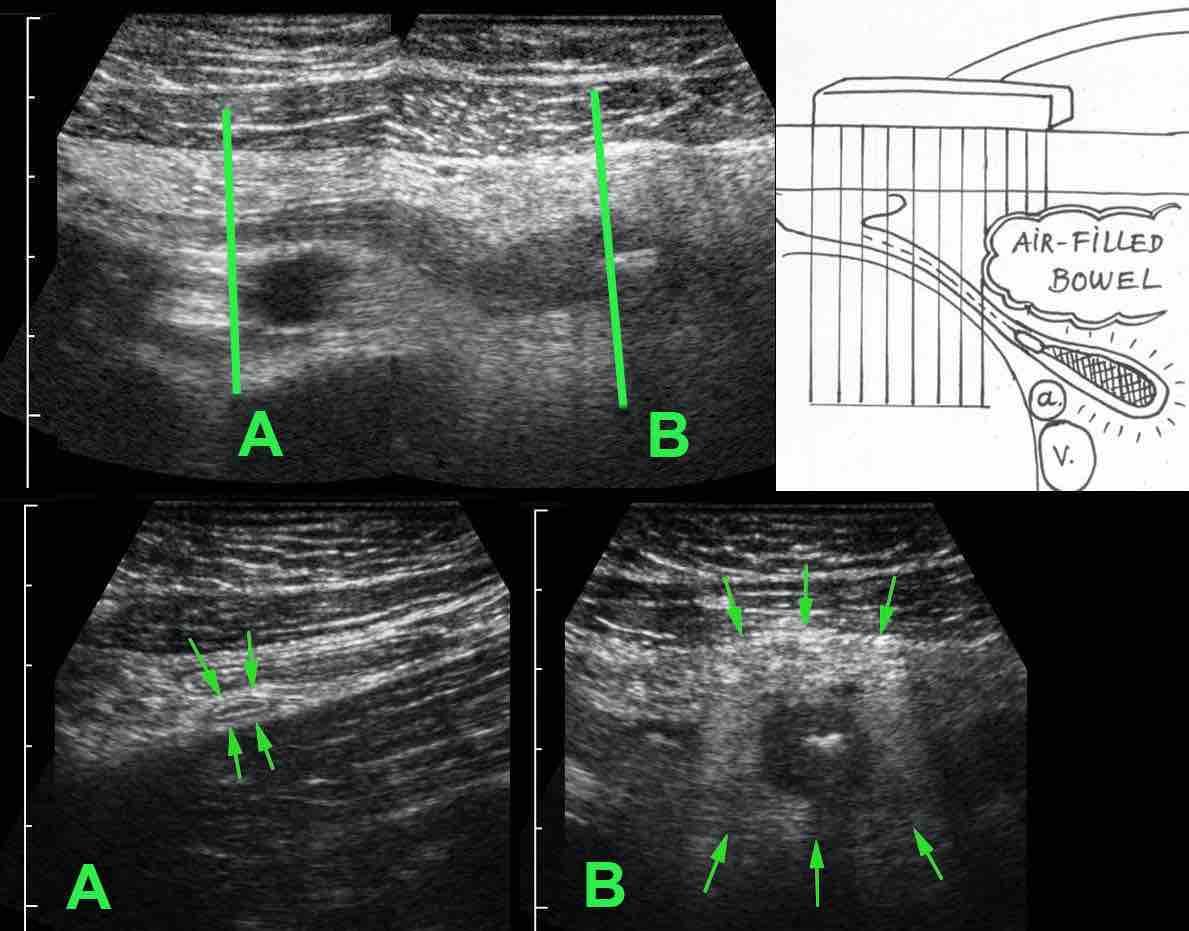

Một bẫy khác là viêm đầu ruột thừa, trong đó tình trạng viêm chỉ khu trú ở đầu xa của ruột thừa.

Nếu chỉ quan sát được phần gần bình thường (mũi tên trong A), trong khi đầu xa (mũi tên trong B) bị che khuất bởi hơi ruột, có thể dẫn đến chẩn đoán âm tính giả. (a và v = động mạch và tĩnh mạch chậu)